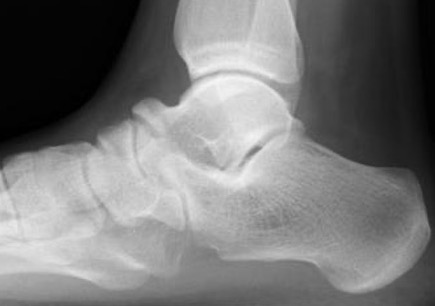

Xray

| Talar beaking | C Sign | Harris axial view | Ball and socket ankle joint |

|---|---|---|---|

| Traction spur due to increased stress | Medial outline talar dome and posterior sustenaculum tali |

40 degree axial view Ski jump view Visualize middle facet |

Secondary to rigid subtalar joint Develops to allow inversion / eversion |

Talar beaking with C sign